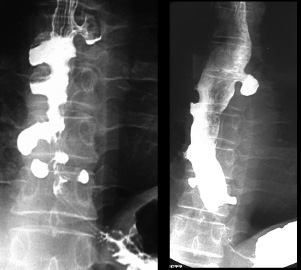

Image radiologique une DES . Les

spasme de owsophage le plus souvent situe au portion

inferieure de oesophage. Bord irregulie et spastique

de oesophage voyait si net le cliche de face |

Image radiologique une DES au

temps d'evacuation de baryte |